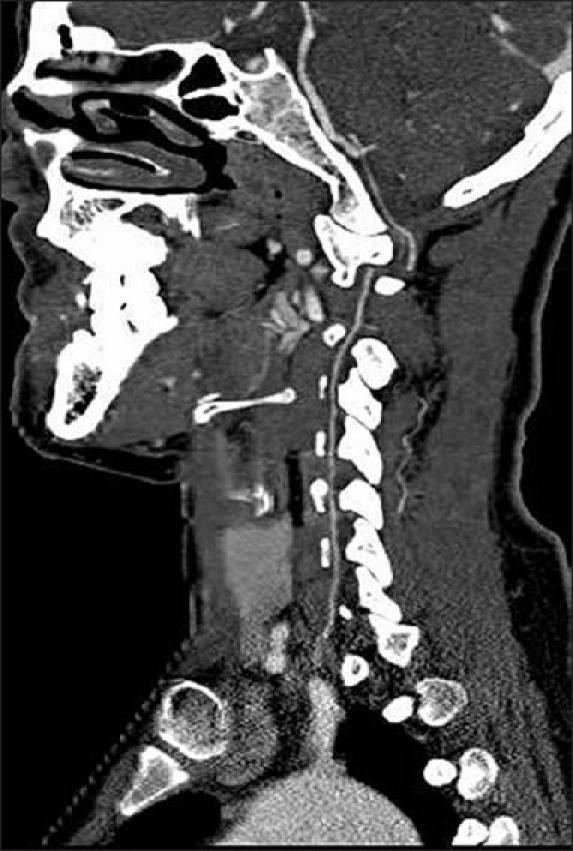

Vertebral artery injury after cervical spine trauma: A prospective study using computed tomographic angiography.

We performed a prospective study using computed tomographic angiography (CTA) to determine the frequency of VAI associated with cervical spine injuries and investigate the clinical and radiological characteristics. Between January 2005 and August 2007, 99 consecutive patients with cervical spine fractures and/or dislocations were prospectively evaluated for patency of the VA, using the CTA, at the time of injury.

Complete disruption of blood flow through the VA was demonstrated in seven patients with unilateral occlusion (7.1%). There were four men and three women with a mean age of 43 (range, 33-55 years). Unilateral occlusion of the right vertebral artery occurred in four patients and of the left in three. Regarding the cervical injury type, two cases were cervical burst fractures (C6 and C7), two had C4-5 fracture/dislocations, two had a unilateral transverse foraminal fracture, and one had dens type III fracture. All patients presented with good patency of the contralateral VA. None of the patients developed secondary neurological deterioration due to vertebrobasilar ischemia during the follow-up period with a mean duration of 23 months.

VAI should be suspected in patients with cervical trauma that have cervical spine fractures and/or dislocations or transverse foramen fractures. CTA was useful as a rapid diagnostic method for ruling out VAI after cervical spine trauma.